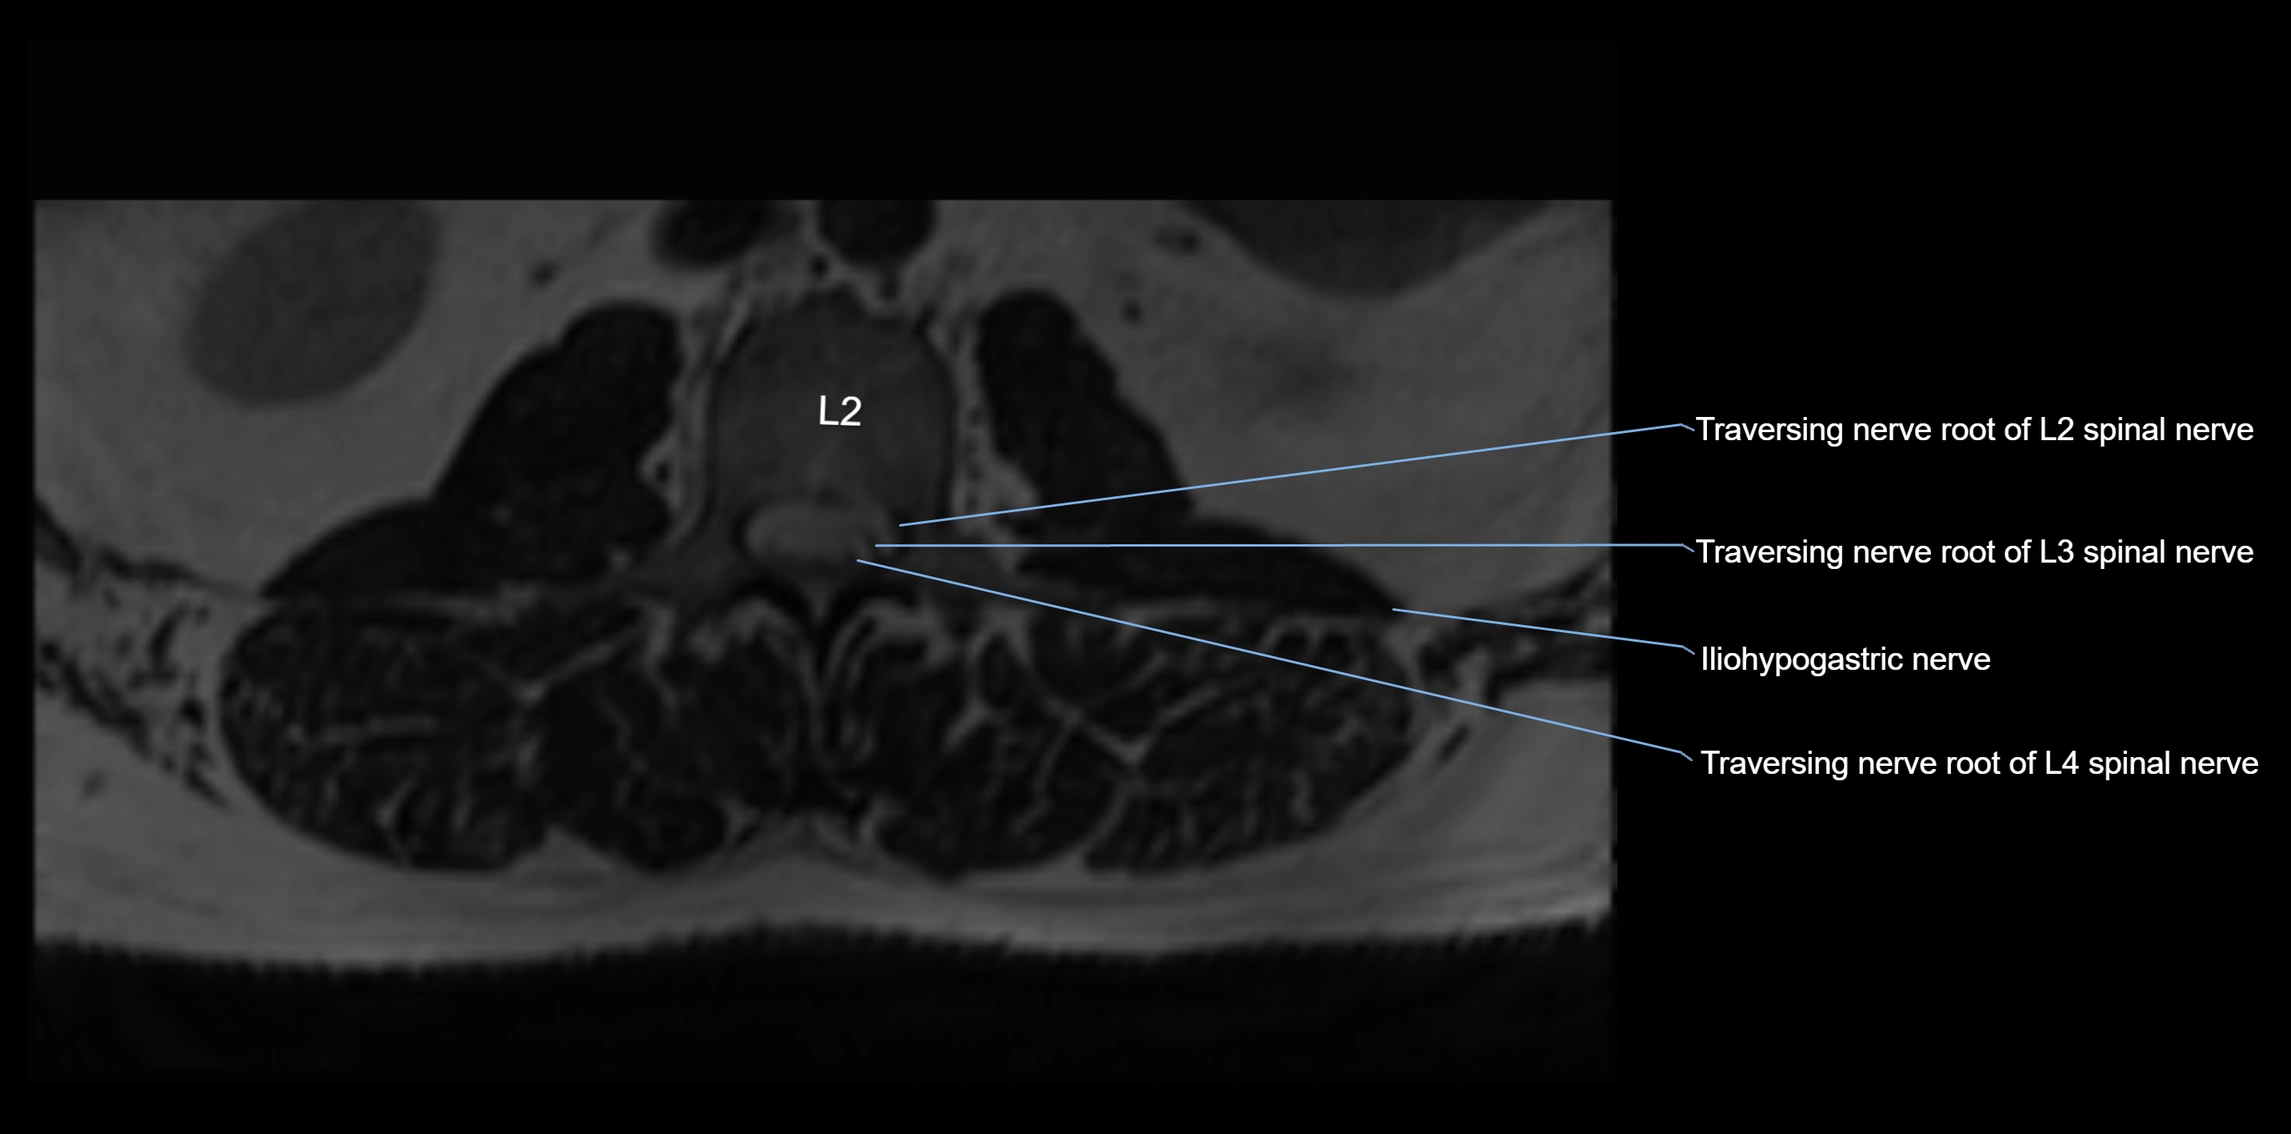

MRI Appearance

T1-weighted images:

• Nerve appears as a very thin low-to-intermediate signal intensity structure

• Surrounded by bright fat, aiding visualization

T2-weighted images:

• Nerve shows intermediate to mildly hyperintense signal compared to muscle

• Pathological involvement appears brighter

STIR (Short Tau Inversion Recovery):

• Normal nerve appears dark

• Inflamed or entrapped nerve appears bright hyperintense

T1 Fat-Sat Post-Contrast:

• Normal nerve enhances minimally

• Pathologic nerve (neuritis, entrapment, tumor infiltration) shows focal or diffuse enhancement

3D T2 SPACE / CISS:

• Nerve appears intermediate to mildly hyperintense compared to muscle

• Surrounded by bright fat or CSF, improving visualization

• Best sequence for mapping small pelvic nerves such as the anococcygeal

MRI image

image